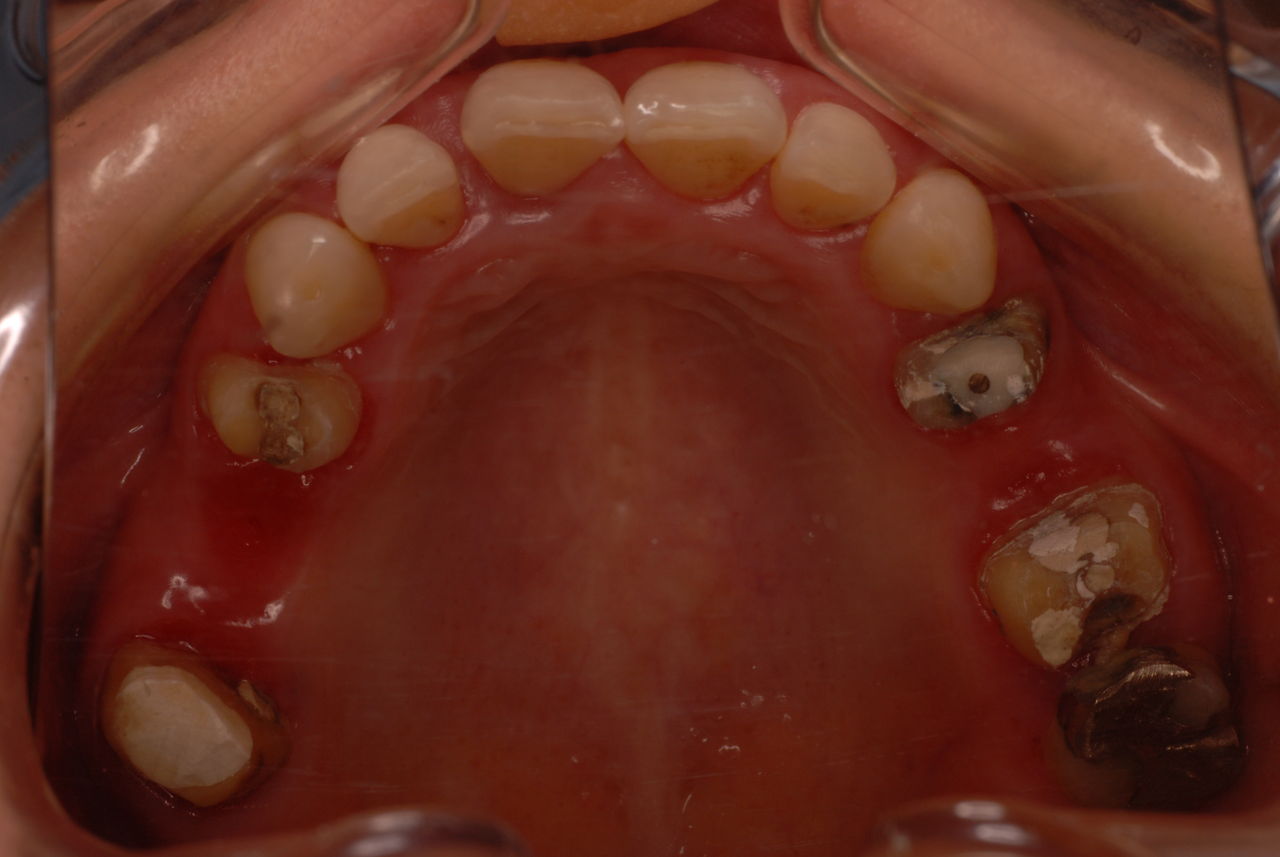

今日のすべての患者さんは、一人を除いて新患を含めてすべて歯周病の方でした。

歯周病は殆どの方に存在し、気づかないうちに進行していきます。

そして場所や痛みなどの症状がはっきりしないのです。冷たい水がしみることもあります。

なかなかブラシの使い方ができていないようで、歯磨きと歯周病でのブラシの使い方は別なのですが、習ったことも検査もされずに金属を被せたりしているようで、これからも歯医者さんで抜かれたり、その後にインプラントのような高価な“クギ”を打ち込まれる方が増えるかと思うと残念です。

まず検査をして、ブラシの使い方を習得して歯医者さんで削ったり抜かれたりしないように予防に注意する方々が増えないかと思う日々です。

被せても、詰めても病気は治らないのですから。又病気の元になり易い不適合な差し歯や金属、インプラントがあればそこからバイキンが侵入して体に悪さもしやすいのではないかと心配しています。